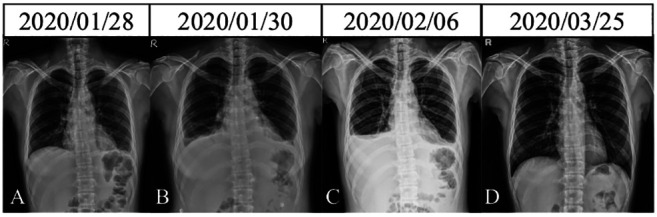

Case report: This is the case of a 49-year-old Taiwanese female diagnosed with SLE, alongside pericarditis, pleuritis, and multi-organ impairments. Despite initial treatment and intermittent follow-ups, the patient experienced recurrent disease exacerbations, which was managed with immunomodulatory therapies. In October 2024, molecular hydrogen supplementation was introduced as an adjuvant therapy. Immunophenotypic analysis revealed dynamic changes in the percentages of immune cells, with decreasing trend of Tr1 cells and increasing trend of naïve Treg cells, B cell subsets expressing Fas, and transitional B cells following molecular hydrogen therapy.